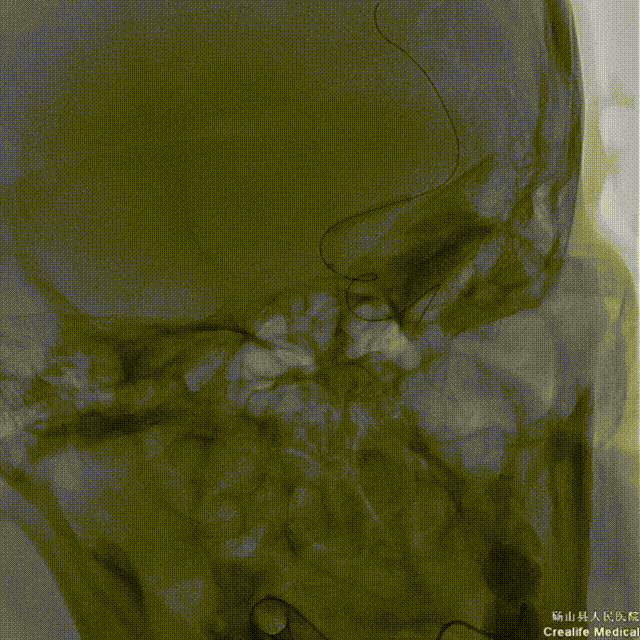

➤经股动脉入路造影影像

II型弓,左侧大脑中动脉M1段重度狭窄(几近闭塞)。

➤手术过程

微导丝带领微导管通过左侧大脑中动脉狭窄段。

微导管冒烟证实在血管真腔内。

沿微导丝将赛诺NOVA®颅内药物洗脱支架 2.5*15mm送至左侧大脑中动脉狭窄段,造影定位准确。

缓慢扩张球囊/释放支架。